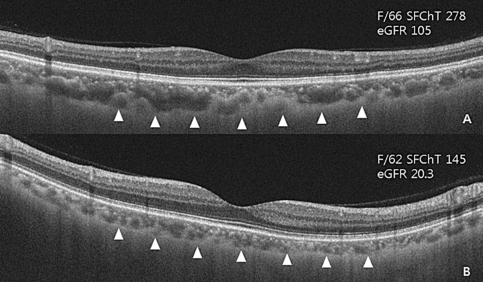

In simple linear regression analysis, SFChT of normal fellow eyes was significantly associated with BMI (P = 0.028), age (P = 0.003), serum osmolarity (P = 0.035), creatinine (P = 0.002), estimated GFR (estimated glomerular filtration rate) (P < 0.001), and phosphorus levels (P = 0.016). Stepwise multiple linear regression revealed that SFChT had a significant positive correlation with eGFR (P < 0.001; Table 3, Fig. 1).

Representative swept-source optical coherence tomography image of a contralateral normal eye in patients with retinal vein occlusion. A. 66-year-old female patient with retinal vein occlusion. Estimated glomerular filtration rate (eGFR) was 105 mL/min/1.73 m2; subfoveal choroidal thickness was 278 μm. B. 62-year-old female patient with retinal vein occlusion. Estimated glomerular filtration rate (eGFR) was 20.3 mL/min/1.73 m2; subfoveal choroidal thickness was 145 μm. Arrow heads indicate chorioscleral interface.